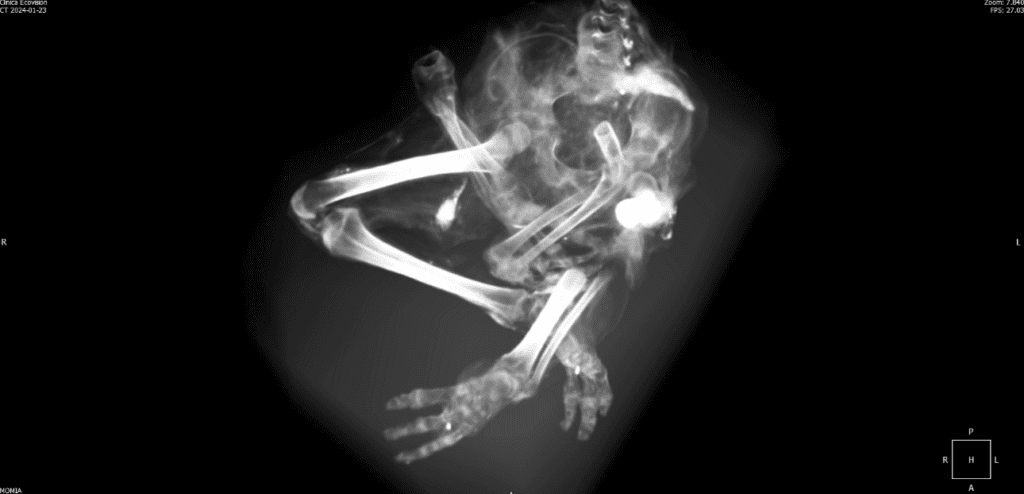

Do these Nazca mummies represent the true form of a once-living biological species, or are they something else entirely?

Are these bodies works of art or intentional hoaxes made of a mish-mash of animal bones? Are they human bodies that have suffered the indignity of ancient or modern modification? Maybe some of both?

Or do these bodies represent the remains of formerly unknown species (plural) that once lived and breathed in the Nazca region?

If you’ve been following this story, you would know that many educated professionals and doctors believe these bodies to be the remains of real organisms. At the recent press conference in Lima on April 4, 2024, you heard from Dr. David Ruiz, a plastic surgeon and forensic specialist from Peru. You also heard from Dr. Jose Zalce Benitez, a Mexican Navy Forensic doctor. These doctors have resumes a mile kilometer long, and they have examined these bodies in person, with CT scans, X-rays, tomography, etc. They have not detected manipulation of the bodies.